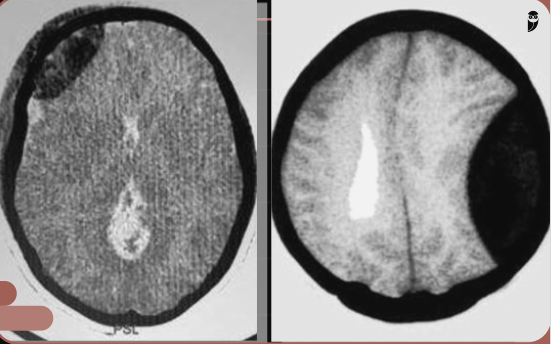

Qual é o tipo de sangramento que a imagem a seguir mostra?

Hematoma subdural crônico.

Hemorragia subaracnóidea.